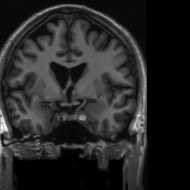

4.3 Medical Image Compressive Sensing

Medical image compressive sensing is an everlasting practical application in image reconstruction area. In this section we test the performance of the proposed ResGD-Net on compressive sensing reconstruction of brain MR images [3] (CS-MRI). In CS-MRI problem, the data fidelity term is f(𝐱;𝐳)=Φ𝐱𝐳22𝑓𝐱𝐳subscriptsuperscriptnormΦ𝐱𝐳22f(\mathbf{x};\mathbf{z})=\|\Phi\mathbf{x}-\mathbf{z}\|^{2}_{2}, where Φ=𝒫Φ𝒫{\Phi}=\mathcal{P}\mathcal{F}, 𝒫𝒫\mathcal{P} is a binary selection matrix representating the sampling trajectory, and \mathcal{F} is the discrete Fourier transform. We randomly pick 150150150 images from the brain MRI datasets [3], then crop and keep the central 190×190190190190\times 190 part with less background. Then we at random divide the dataset to 100100100 images for training and 505050 for testing. Among this section, we present the comparison results between ResGD-Net and ISTA-Net+ [33], where the latter one is a state-of-the-art method in tackling with CS-MRI problem. For fairness, both algorithms compared here are evaluated on the same dataset and metrics. Experiments are conducted across different sampling ratios 10%percent1010\%, 20%percent2020\% and 30%percent3030\% of 𝒫𝒫\mathcal{P} to show the generality. The study of ResGD-Net on different sampling ratios and various phase numbers is shown in Fig. 4. The PSNR comparison with ISTA-Net+ is shown in Table. 2. The result enhancement of the proposed ResGD-Net against ISTA-Net+ is remarkable across all sampling ratios even though we only use approximately 10%percent1010\% many number of parameters than ISTA-Net+ [33].

In addition, we provide the visualization results of some selected MR images reconstructed by the state-of-the-art ISTA-Net+ [33] and our proposed ResGD-Net on compressive sensing (CS) ratio 10%percent1010\%, 20%percent2020\% and 30%percent3030\%. The results are evaluated under metrics the Peak Signal-to-Noise Ratio (PSNR), the Structural Similarity (SSIM) and the Mean Squared Error (MSE). For better visualization, we rescale the pixel value by multiplying 8.0×8.0\times on the error maps (the second row of Figs. 5 - 7) when displaying.

Refer to caption

(a) ISTA-Net+

PSNR: 29.0929.0929.09dB

SSIM: 0.89190.89190.8919

MSE: 1.231e31.231𝑒31.231e-3

(b) ResGD-Net

PSNR: 32.2532.2532.25dB

SSIM: 0.91780.91780.9178

MSE: 5.946e45.946𝑒45.946e-4

(c) True

Figure 5: Reconstruction results of a brain MR image [3] with radial mask of CS ratio 10% using the state-of-the-art ISTA-Net+ [33] and the proposed ResGD-Net. The figures in the second row are the difference images compared to the true image